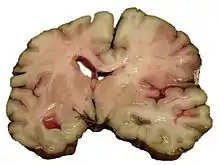

Intracerebral hemorrhage

It generally occurs in small arteries or arterioles and is commonly due to hypertension,[51] intracranial vascular malformations (including cavernous angiomas or arteriovenous malformations), cerebral amyloid angiopathy, or infarcts into which secondary hemorrhage has occurred.[2] Other potential causes are trauma, bleeding disorders, amyloid angiopathy, illicit drug use (e.g., amphetamines or cocaine). The hematoma enlarges until pressure from surrounding tissue limits its growth, or until it decompresses by emptying into the ventricular system, CSF or the pial surface. A third of intracerebral bleed is into the brain's ventricles. ICH has a mortality rate of 44 percent after 30 days, higher than ischemic stroke or subarachnoid hemorrhage (which technically may also be classified as a type of stroke[2]).